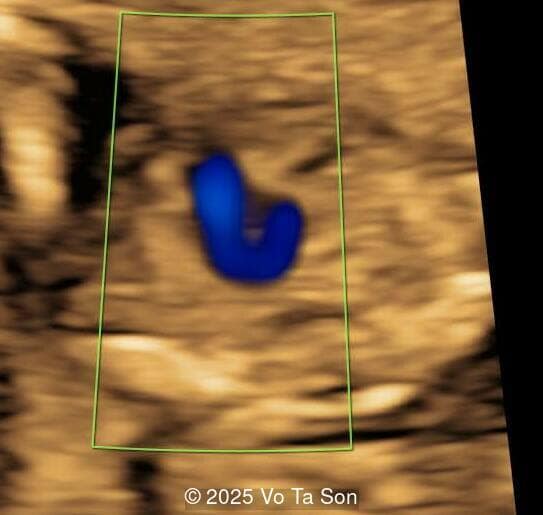

3D Image

Image 2 3D Image

Spinal defect in the sacral region visualized on 3D ultrasound.

Image 3 Spinal defect in the sacral region visualized on 3D ultrasound.